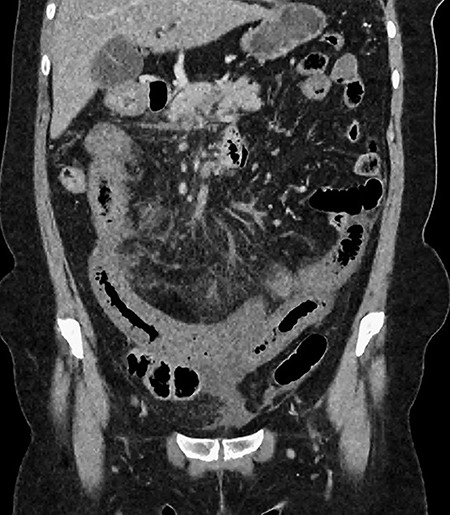

A 61-year-old female presented to a regional hospital with a 3-week history of intermittent diarrhoea, vomiting and generalized abdominal pain. She had a diffusely tender abdomen but was not peritonitic, and was shocked with a heart rate of 110 beats per minute, blood pressure of 89/45 mmHg and was peripherally cool. Her blood tests revealed a lactate of 7.2 mmol/L, which worsened to 7.8 mmol/L during resuscitation with intravenous fluids, and white cell count was 30.9 × 109/L, with an international normalized ratio (INR) of 1.4. She had an acute kidney injury with a creatinine of 119μmol/L and estimated glomerular filtration rate (eGFR) of 43 mL/min/1.73m2. Computed tomography (CT) revealed extensive thickened loops of non-enhancing small bowel with pneumatosis, moderate free fluid and a large splenic infarction. There was extensive thrombosis of the splenic vein and superior mesenteric vein extending into the portal vein to the level of the porta hepatis. Her background history included factor V Leiden and protein S deficiency, for which she had been non-compliant with warfarin during this illness. She had no surgical history (Figs. 1–5).

CT showing an area of splenic infarction due to venous ischaemia.